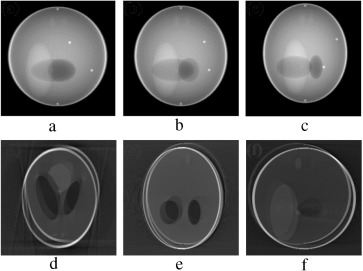

(a–c) Projection at 160°, 180° and 200° source position. (d–f) Axial, coronal ...

Figure 7.

(a–c) Projection at Failed to parse (MathML with SVG or PNG fallback (recommended for modern browsers and accessibility tools): Invalid response ("Math extension cannot connect to Restbase.") from server "https://mathoid.scipedia.com/localhost/v1/":): {\textstyle 160\mbox{°}}

, Failed to parse (MathML with SVG or PNG fallback (recommended for modern browsers and accessibility tools): Invalid response ("Math extension cannot connect to Restbase.") from server "https://mathoid.scipedia.com/localhost/v1/":): {\textstyle 180\mbox{°}}

and Failed to parse (MathML with SVG or PNG fallback (recommended for modern browsers and accessibility tools): Invalid response ("Math extension cannot connect to Restbase.") from server "https://mathoid.scipedia.com/localhost/v1/":): {\textstyle 200\mbox{°}}

source position. (d–f) Axial, coronal and sagittal slices of the translational motion corrupted reconstructed volume.